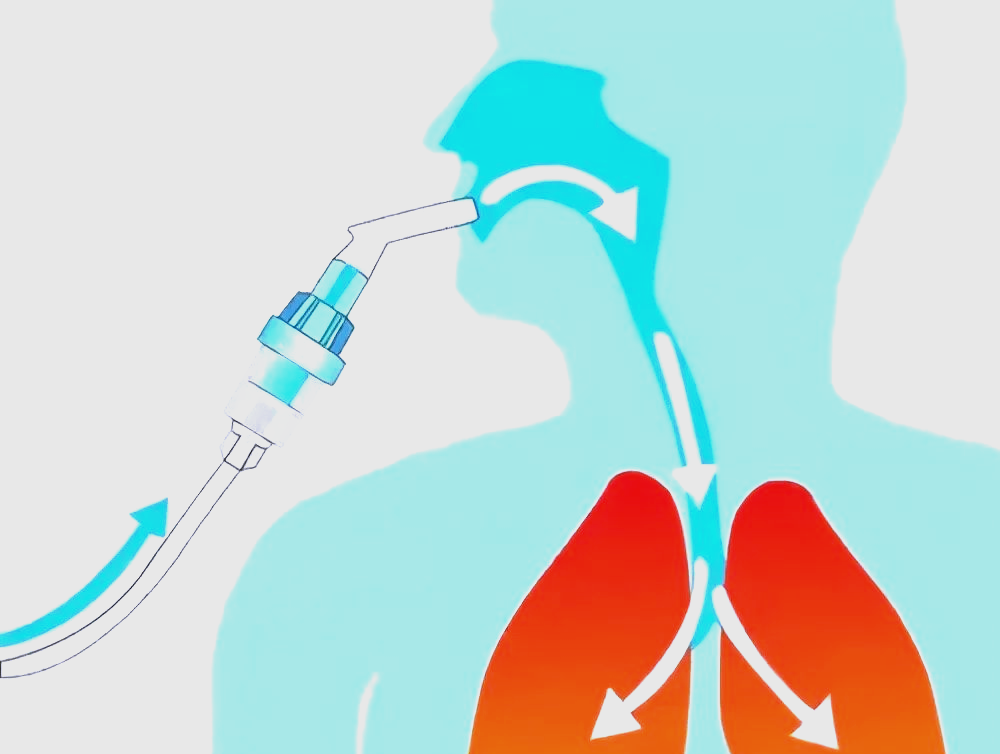

外泌体雾化疗法采用创新的给药途径,通过呼吸道直接递送活性成分。患者吸入雾化后的外泌体悬浮液,这些纳米颗粒可直接沉积于呼吸道黏膜,快速抵达细支气管和肺泡区域,实现精准的局部治疗。